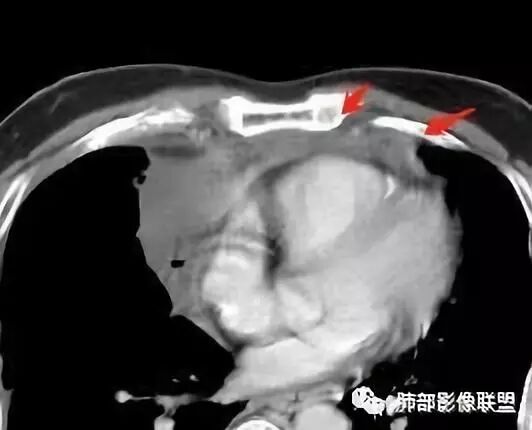

大家仔细看看积液中的游离气体;

不是支气管,是积气;是穿刺进去的;

囊内密度不一致

我认为囊张力高,积液中的气体均在周围,外侧、下方,囊内有间隔:各腔密度不一致;提示:囊腔属于前纵隔,不是包裹性积液;现在的问题:囊腔与内侧的病灶是否是一体的

2、前纵隔内病灶囊实性混杂密度病灶,囊性病灶主要位于右侧,张力较高,有分隔影,囊壁右侧缘光整,病灶左侧实性部分边界不清明显强化,病灶肺瘤交界面大部分边界清楚,部分模糊。